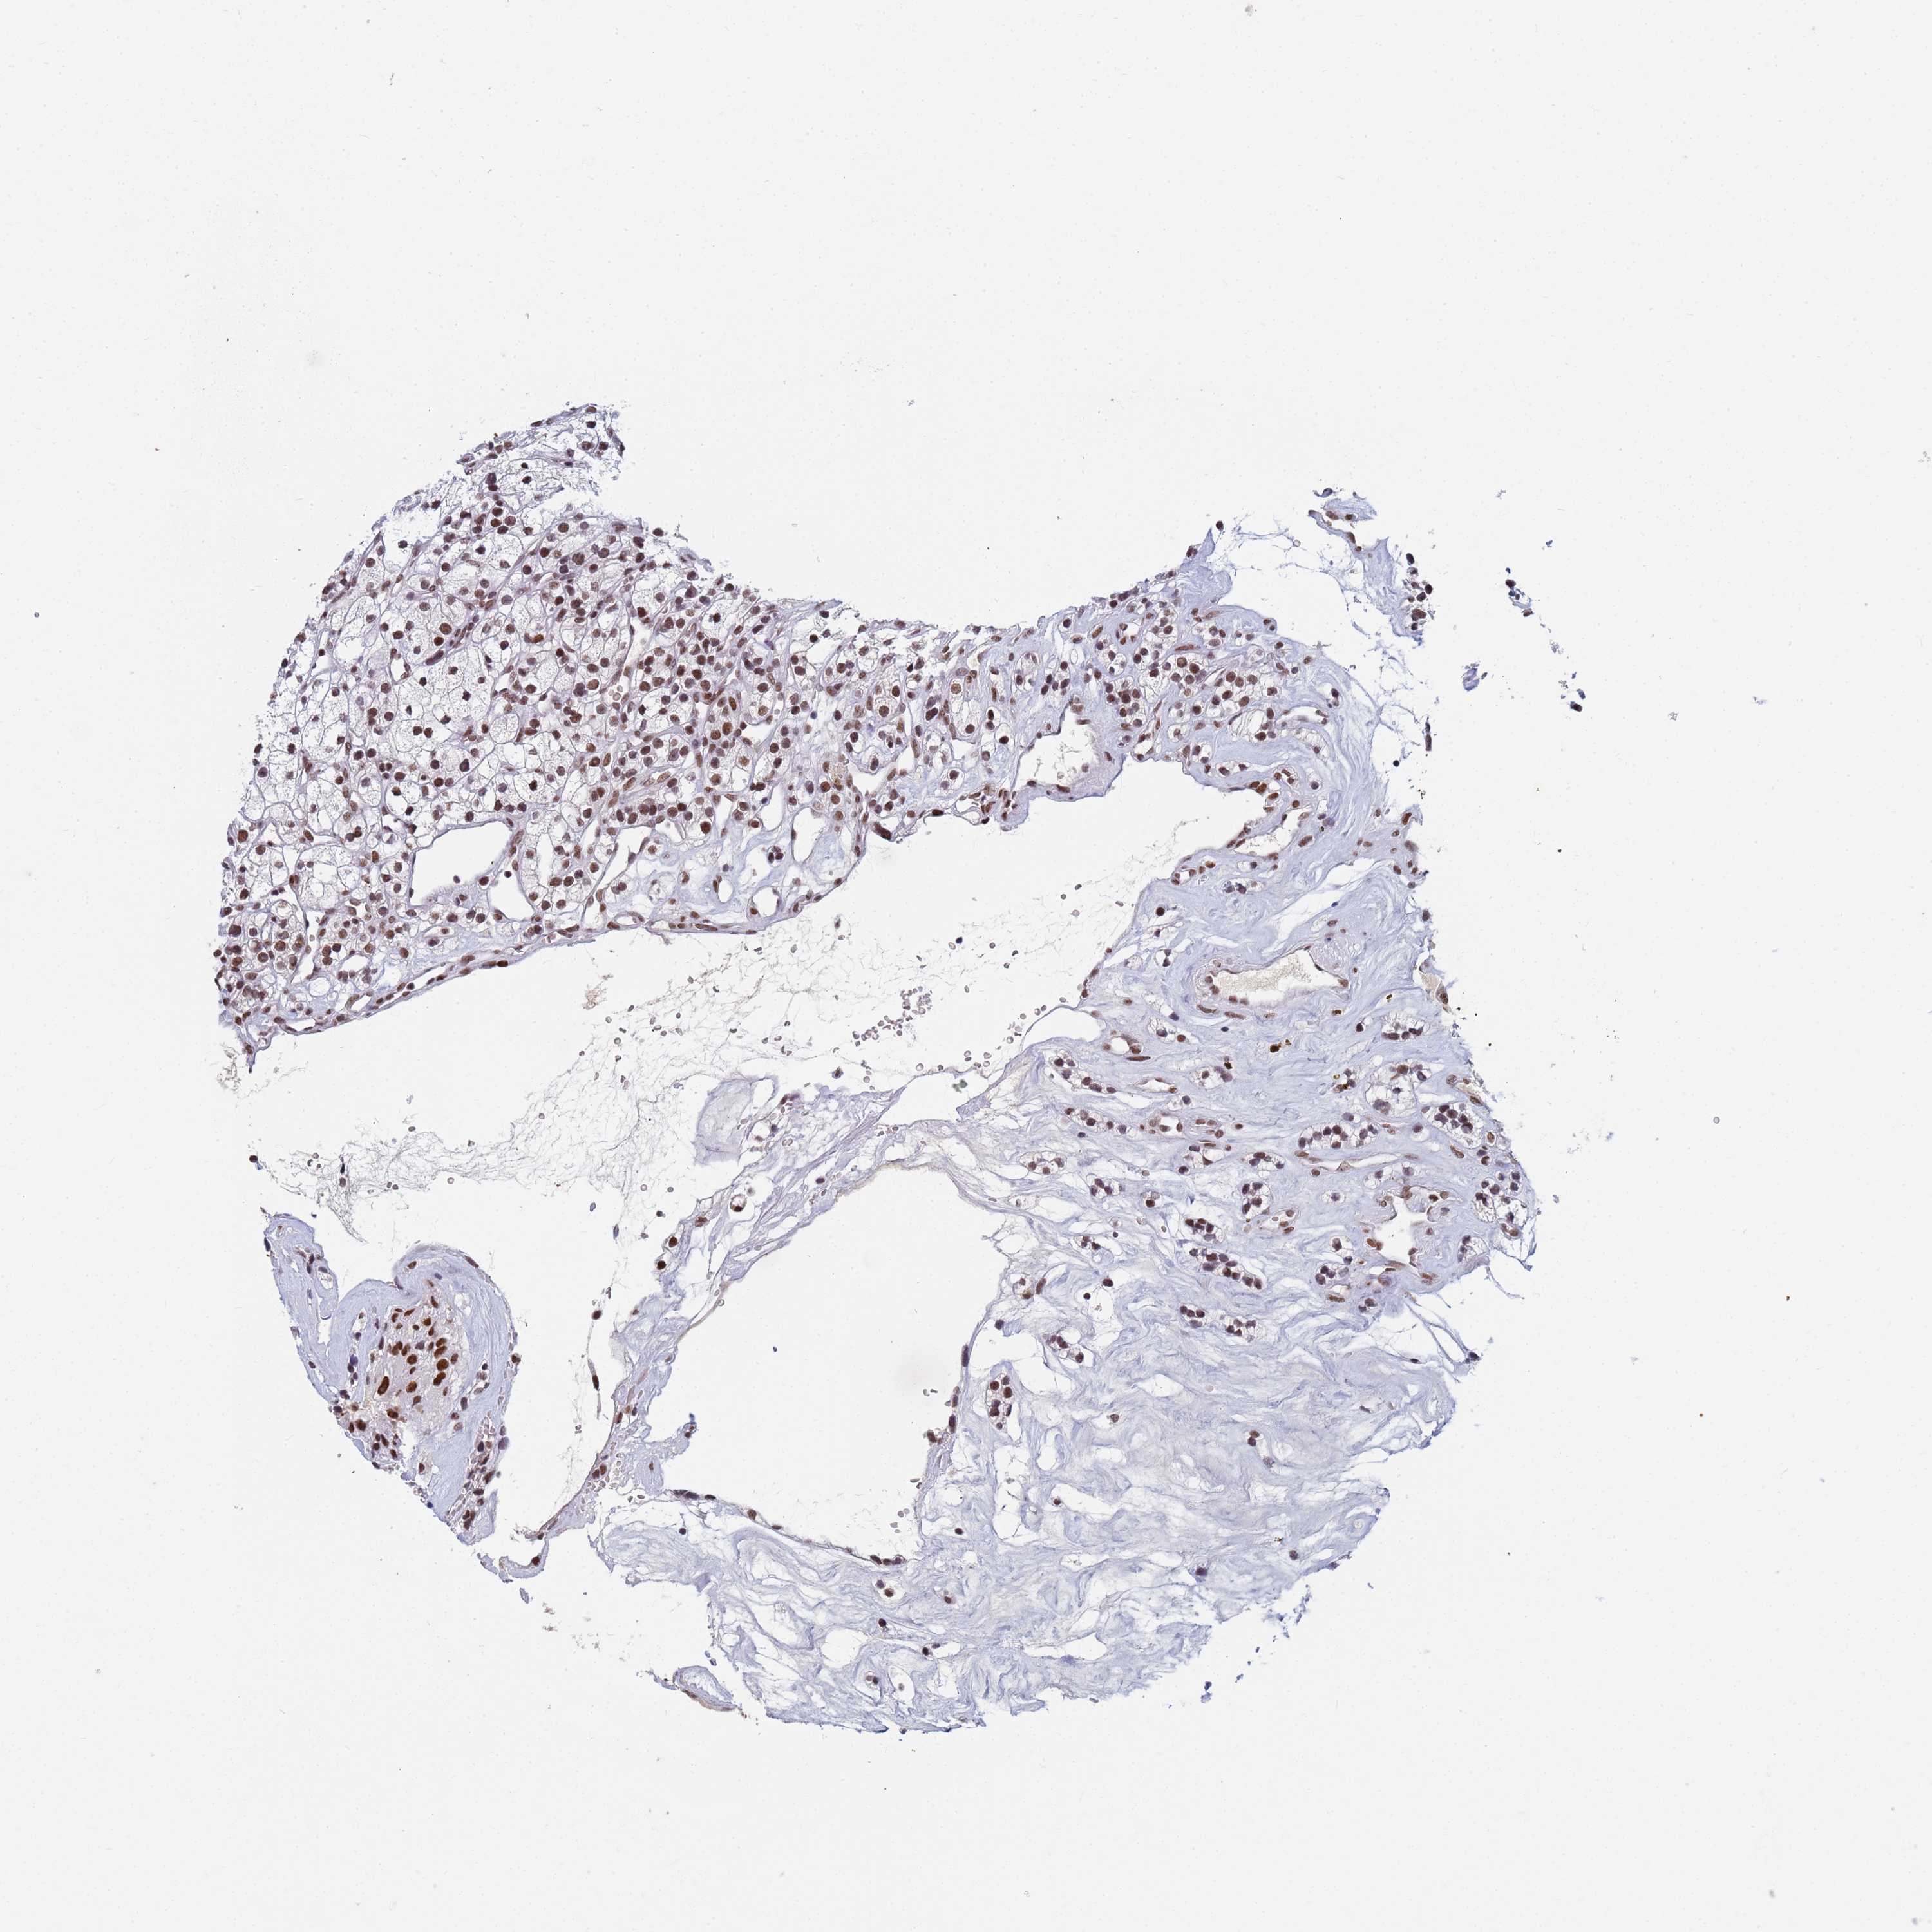

CANCER RENAL CANCER Show tissue menu

KICH TCGA KIRC TCGA KIRC VALIDATION KIRP TCGA PROTEIN RCC CPTAC PROTEIN EXPRESSION